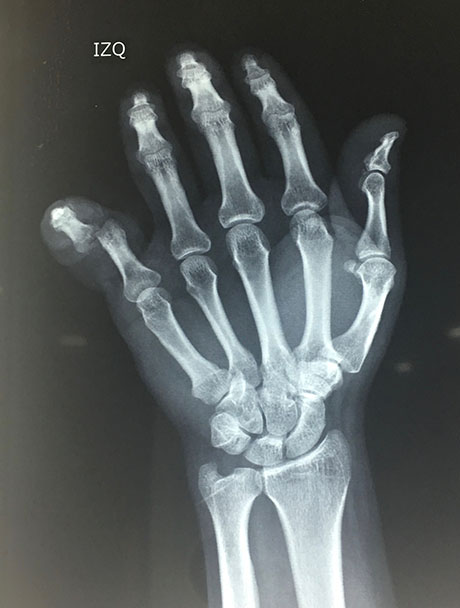

Nuestro paciente mientras ayudaba con el levantamiento de una maquinaria pesada sufre un accidente en que dicha maquina cae sobre su dedo meñique, tras esto se da cuenta que el dedo se ha estallado dejando ver su hueso y una importante herida, nota además deformidad del dedo, es llevado de inmediato a un hospital de la ciudad donde tras ser evaluado y hacerle radiografías le sugieren realizar amputación del dedo pero el paciente no la acepta y decide comunicarse conmigo como cirujano especialista en mano.

Evalué al paciente y siempre pensando en salvar el dedo de la amputación lo lleve a quirófano ese mismo día en horas de la noche, tras una buena limpieza de las heridas encontramos una luxación del dedo y redujimos la misma reparando la parte ligamentaria, mantuvimos al paciente hospitalizado durante 24 horas en que recibió antibióticos y controlamos el proceso de hinchazón del dedo.